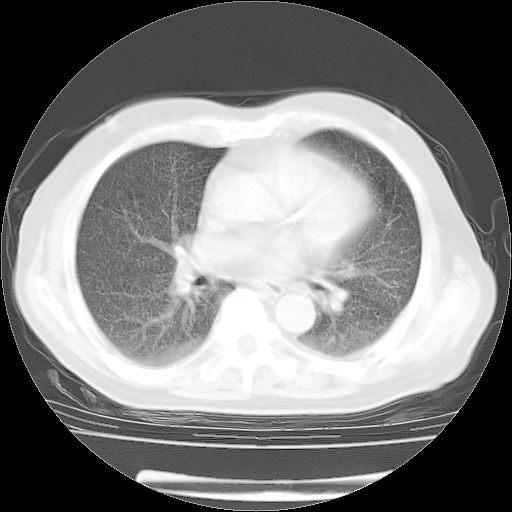

4月28日肺部CT——再次出现类似去年5月9日——透光度降低,(影像科认为)“间质性”改变。

4月28日肺部CT——再次出现类似去年5月9日——透光度降低,“间质性”改变。